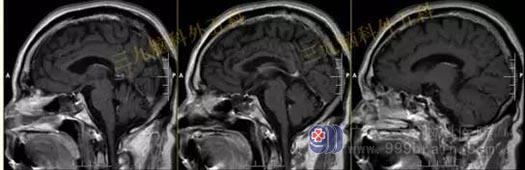

头部MR检查提示:垂体内示一团块状不均匀稍短T1稍短T2异常信号影,FLAIR序列呈稍高、等混杂信号,边界清晰,范围约为2.4×1.5×1.8cm,增强后强化不明显。视交叉受压稍上抬,垂体柄左偏,双侧颈内动脉未见受包绕。

手术过程:内镜下经鼻蝶垂体腺瘤切除术,术中磨除鞍底,有序切除肿瘤,质地硬,沿着肿瘤包膜全切肿瘤,垂体位于左侧,术中垂体保护完整,无海绵窦侵犯。

术后复查头部MR检查提示:原病灶已切除。